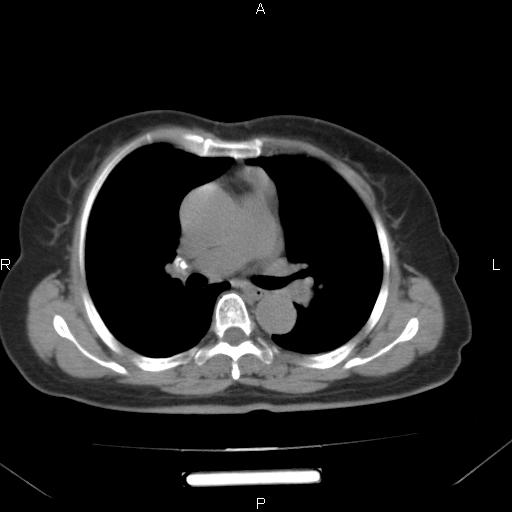

胸腺瘤

女、63Y 双眼睑下垂,早轻晚重。 胸腺瘤???

结果胸腺瘤